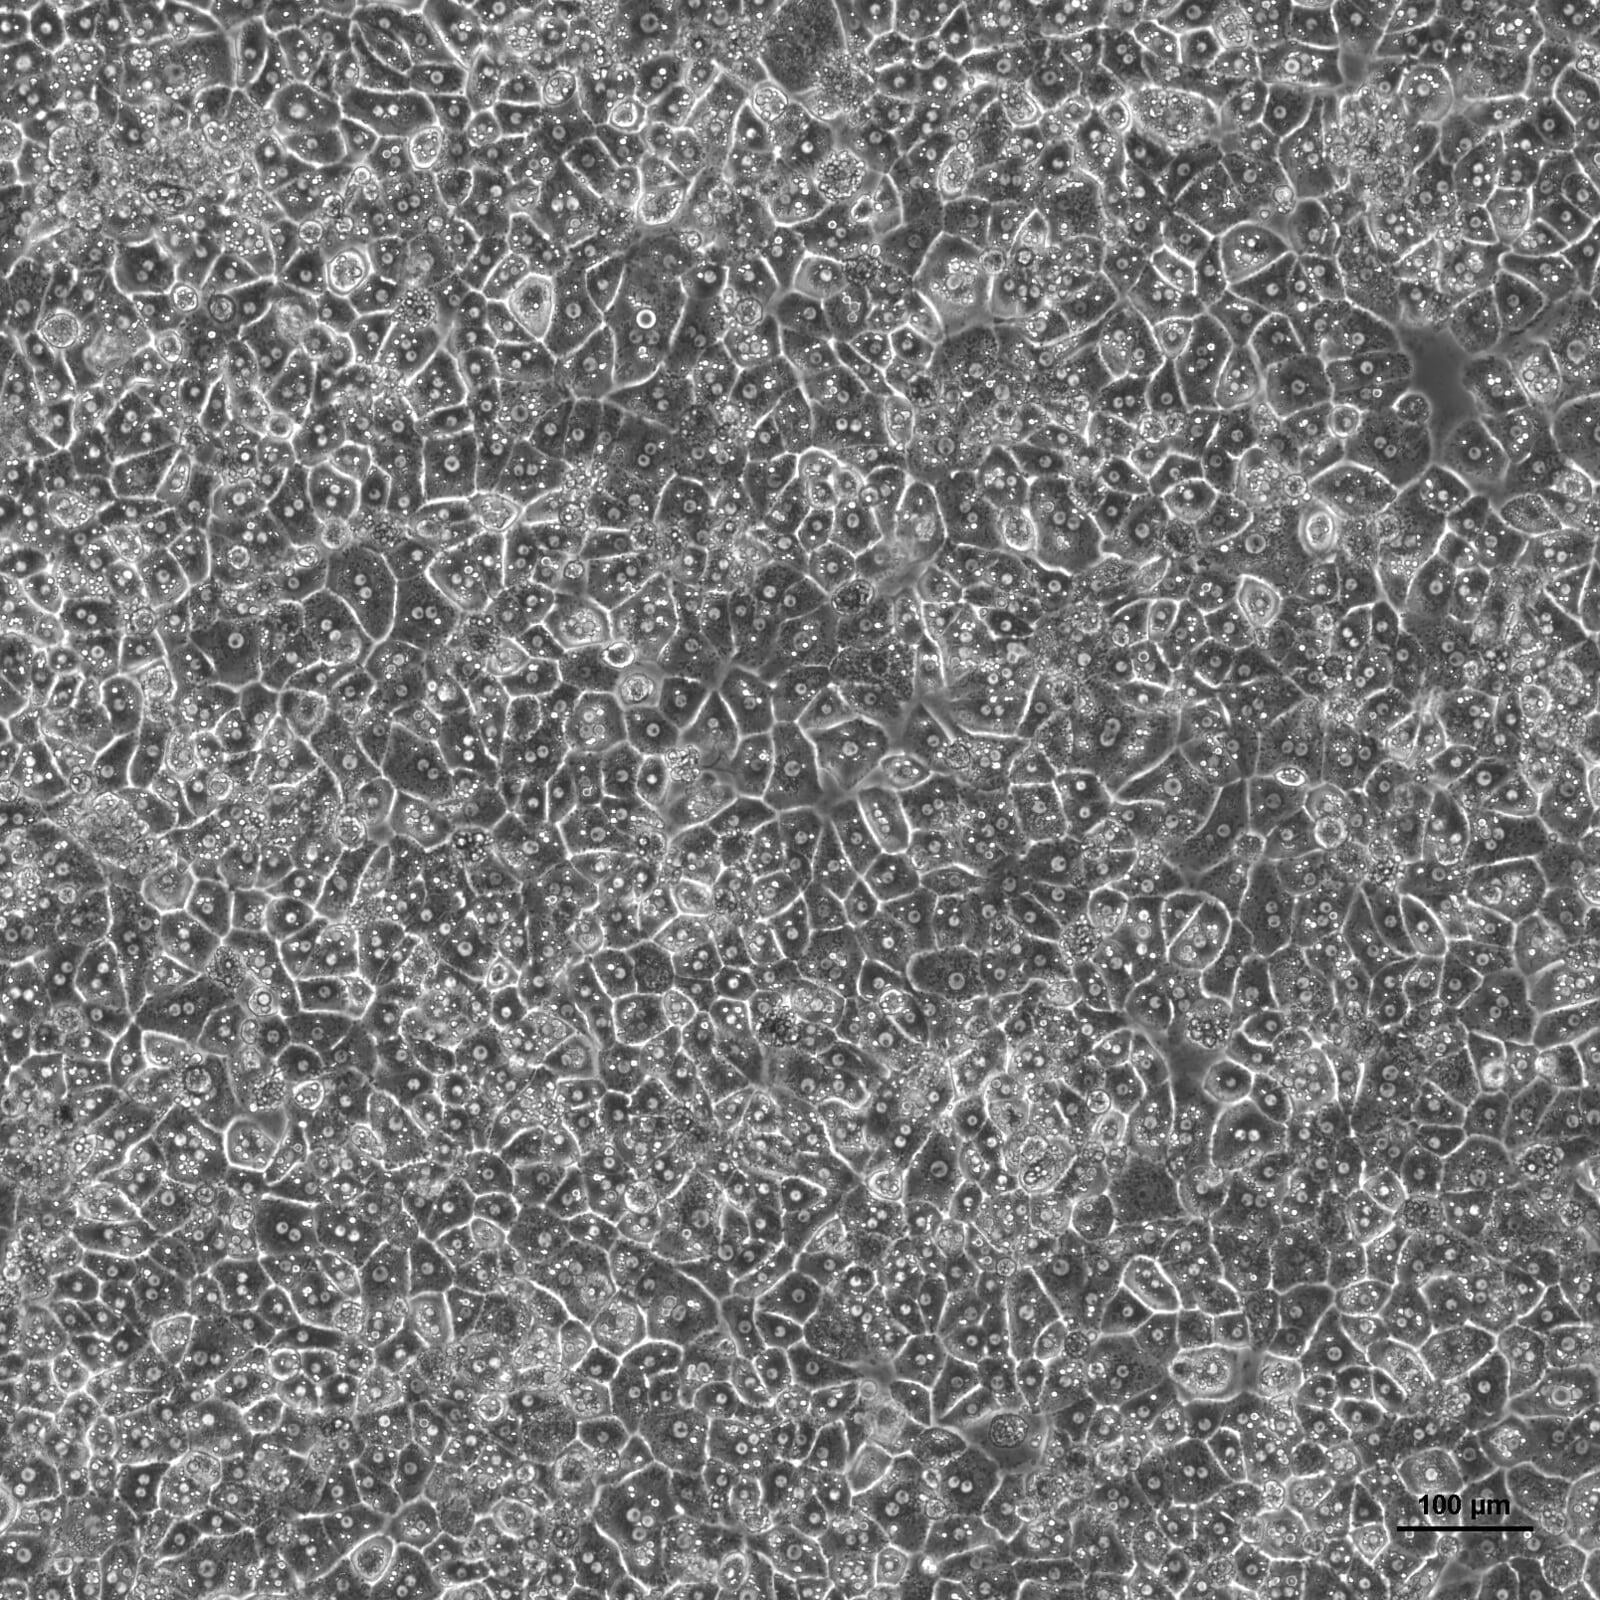

Cytes Biotechnologies’ fresh primary human hepatocytes are isolated from single donors and processed the same day to ensure their best performance. All fresh hepatocytes have post-thaw viabilities over 80%, and each batch is characterized by viability, cell yield, optimal seed density, morphology, attachment efficiency, monolayer confluence, days in culture, and 3D certification. Fresh human hepatocytes are available in multiple formats, from cells in suspension to different well-plates.